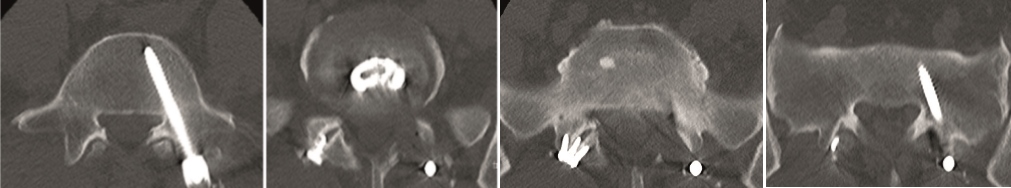

Multilevel facet pathology is shown in Fig 6. Intraoperative and postoperative images are shown (Fig 7-9).